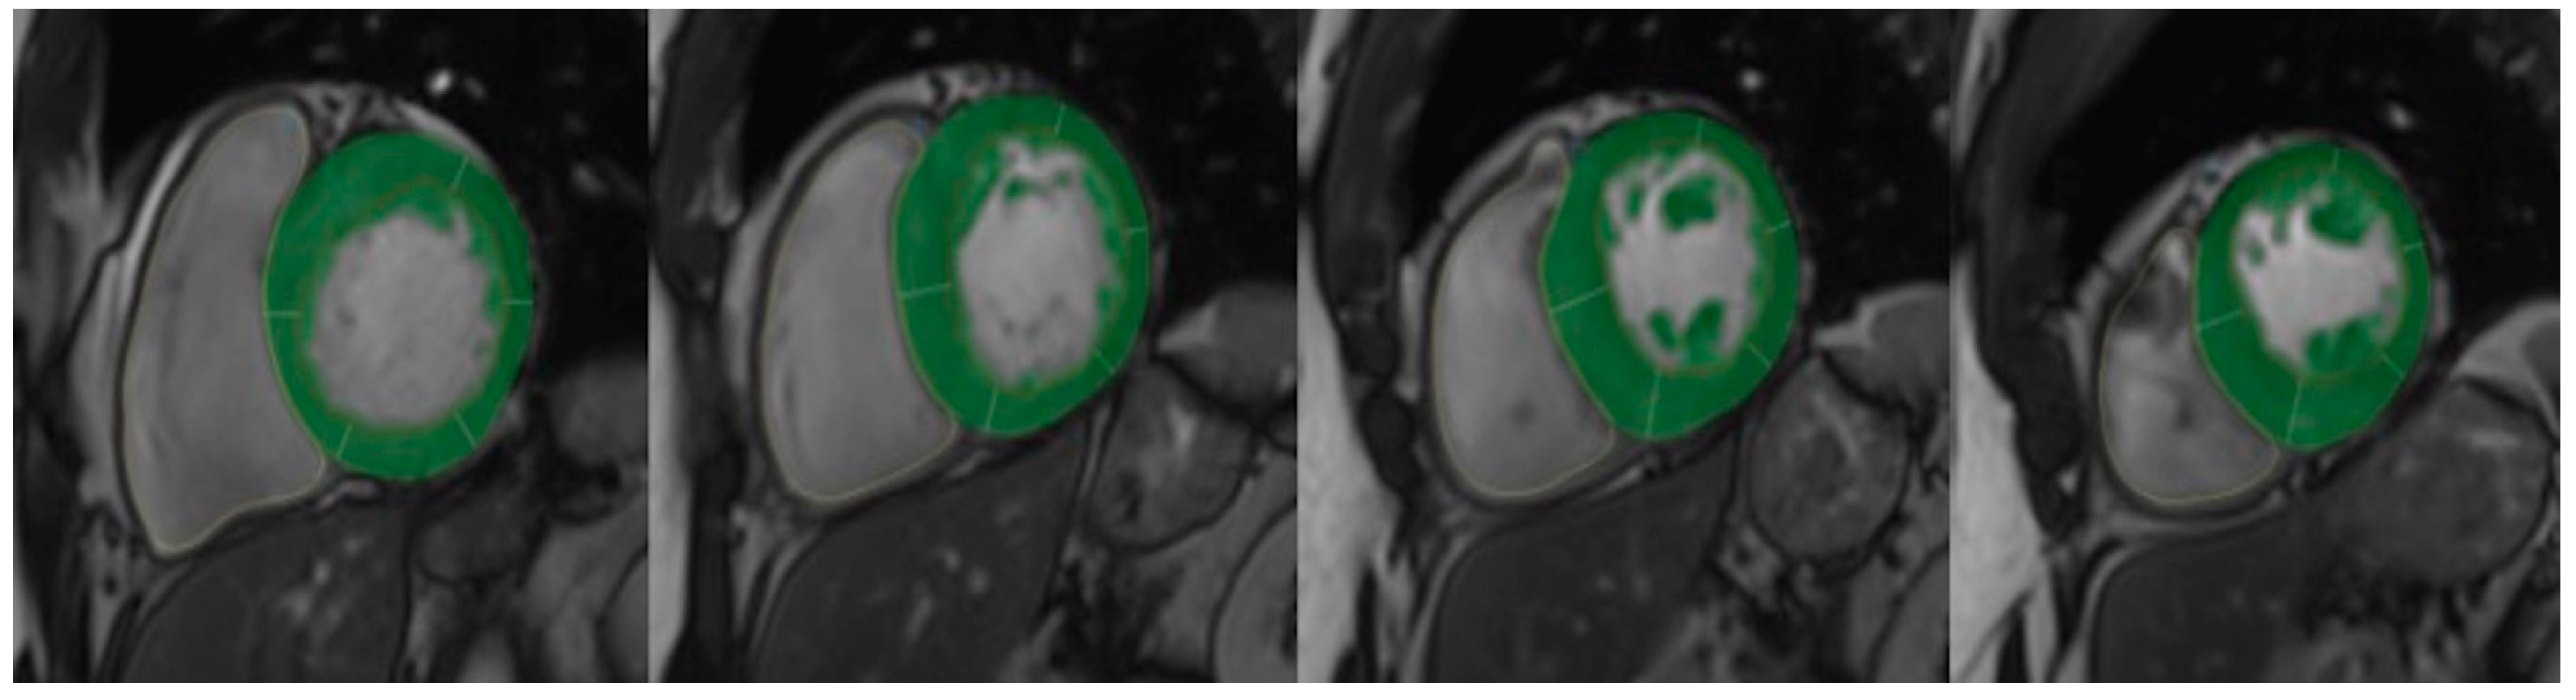

4. Cardiac MRI

6.1. Correlation of LVWT and LVMI with LV Fibrosis